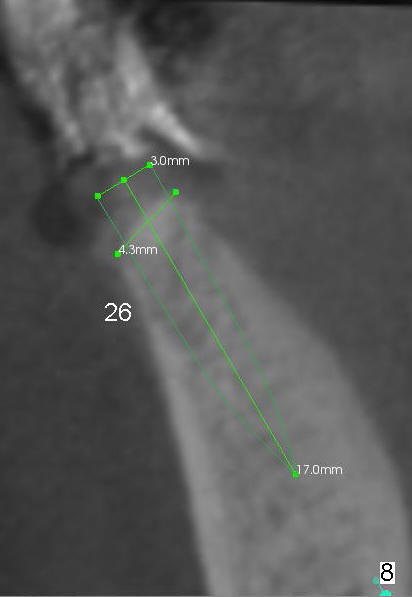

A 85-year-old man has poor dentition (Fig.9). Multiple implants are to be placed at one or two stages (#26-30). If primary stability is obtained for individual implants, they are splinted and immediate provisional is fabricated.

Fig.1-3 are CBCT sagittal sections of the lower right quadrant, whereas Fig.4-8 are coronal sections. The lower left quadrant has been restored.